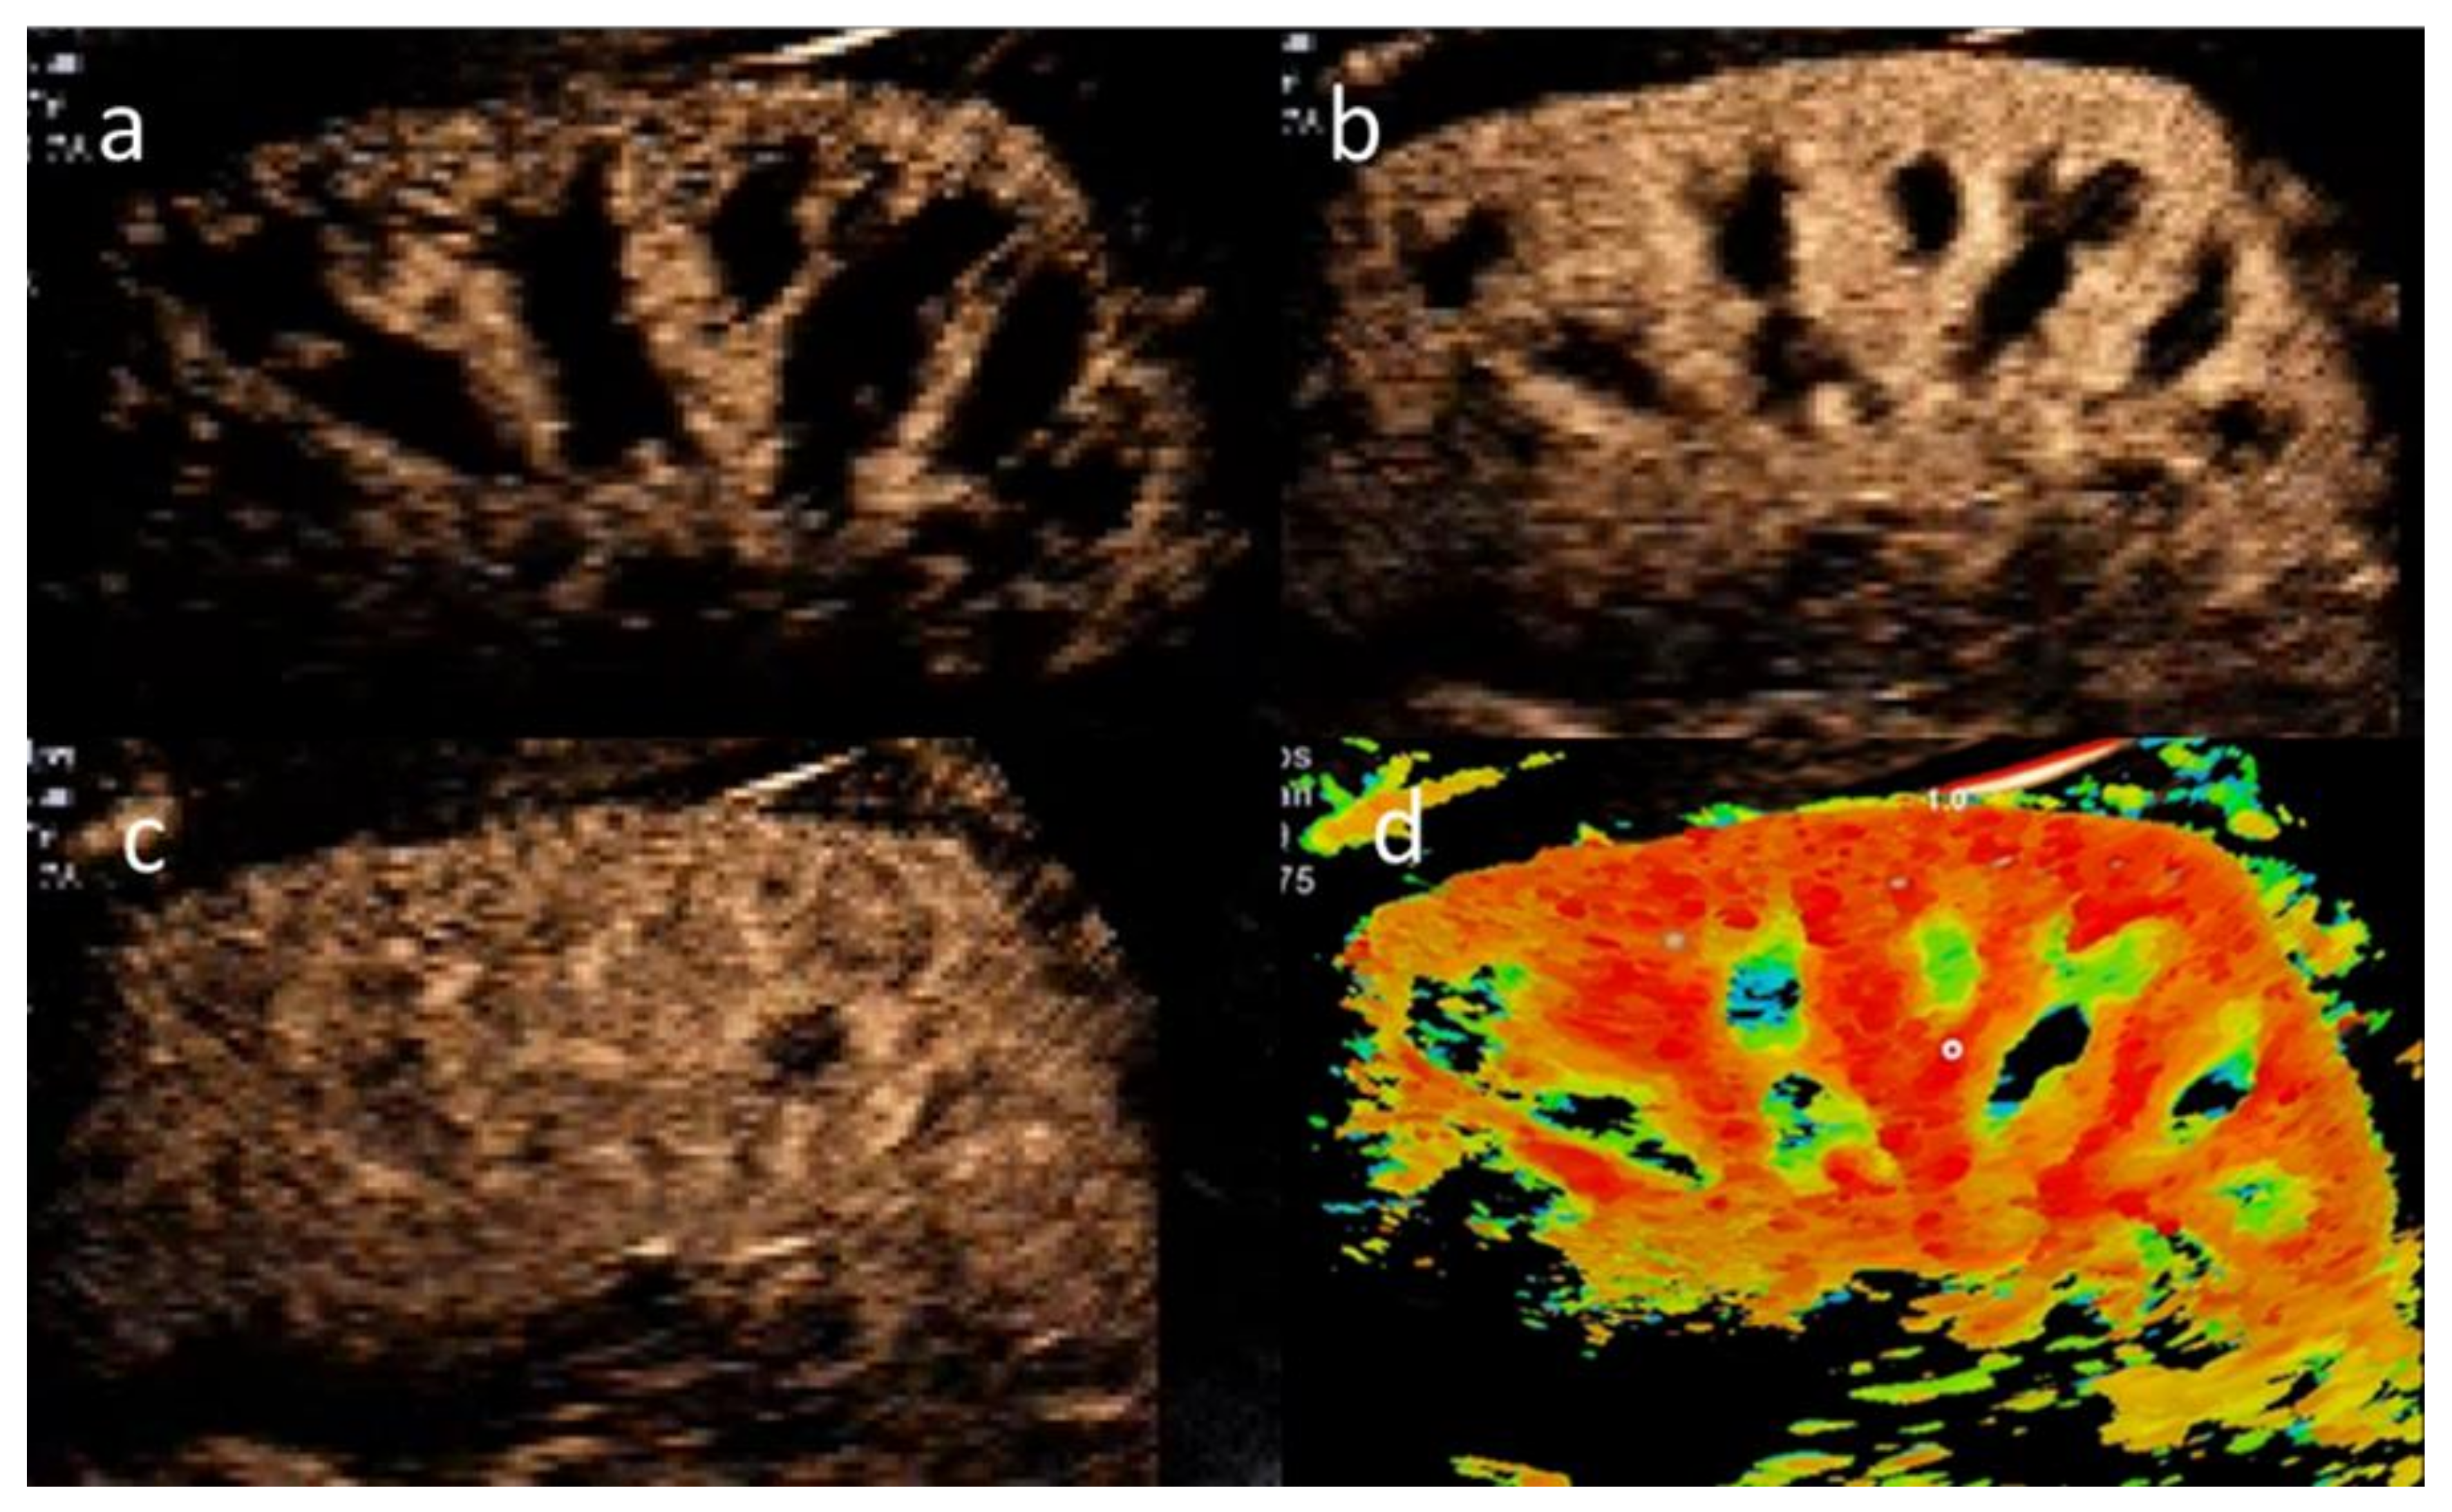

2.2. CEUS Examination Protocol

2.3. Ultrasound Settings